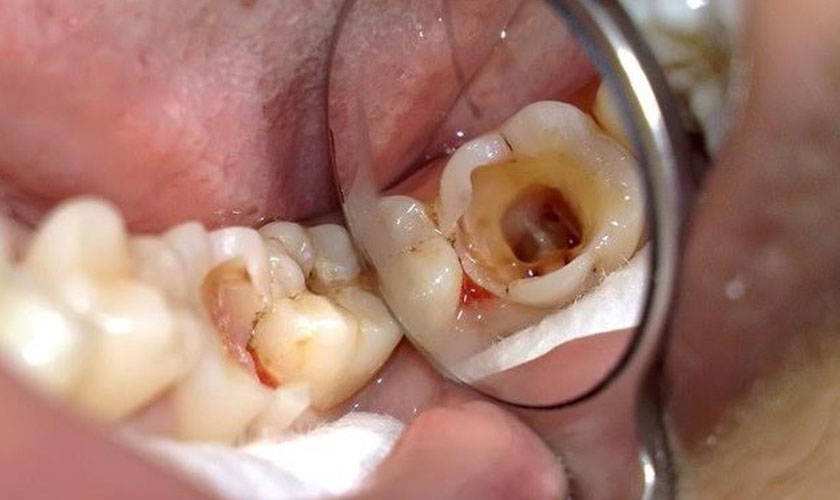

- Sâu răng: Sâu răng ở giai đoạn nghiêm trọng, vi khuẩn tấn công gây nhiễm trùng tủy hoặc sâu răng diện rộng có thể gây ra nhiều biến chứng như đau nhức không ngừng, răng hàm mặt bị sưng to, sốt cao, nổi hạch.

- Viêm tủy răng: Viêm tủy răng là tình trạng tủy răng bị nhiễm trùng do chấn thương hoặc các bệnh lý tạo điều kiện cho vi khuẩn xâm nhập tủy răng và gây viêm nhiễm. Viêm tủy răng gây ra tình trạng đau răng, nổi hạch, hàm sưng to, khó há miệng. Để lâu sẽ kéo theo những biến chứng như áp-xe, viêm mô tế bào, nhiễm trùng máu…

Răng bị viêm tủy do sâu răng nặng